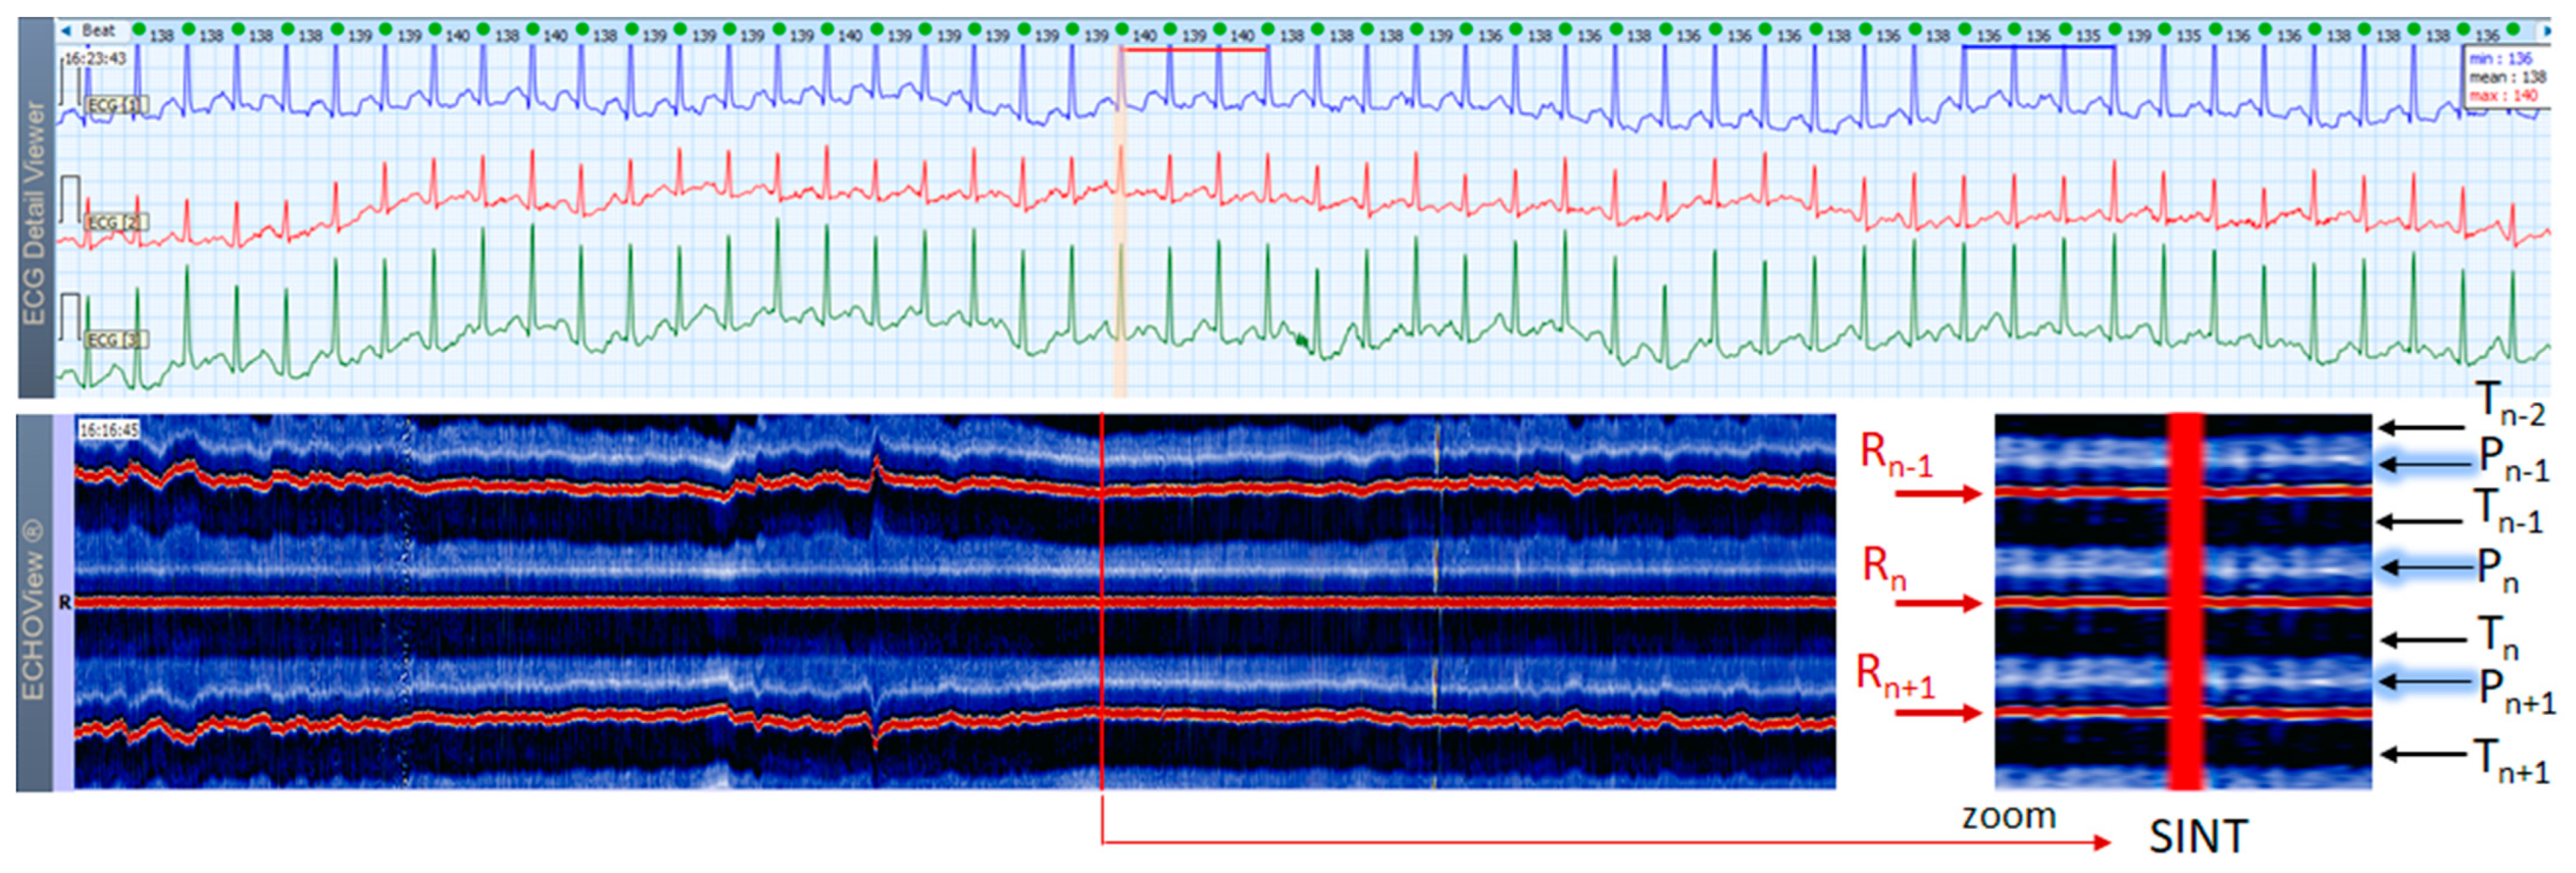

3.3. Sinus Tachycardia Cases

This section interprets together 3-lead Holter ECG strips and the corresponding ECHOView images (ECG lead 1) of three patients with SINT (Figure 6, Figure 7 and Figure 8). When the HR is too high, it is sometimes difficult to differentiate true SINT, caused by a physiological increase in the sinoatrial node activity from SVTs due to re-entry circuits, increased focal atrial automaticity, or triggered activity. The examples below represent somewhat complex cases from an ECG diagnostic perspective, where SINT mimics atrioventricular reentrant tachycardia (AVRT) (Figure 6), or focal atrial tachycardia, atrioventricular nodal reentrant tachycardia (AVRNT) (Figure 8), AFL with AV conduction 2:1 (Figure 6 and Figure 8) or atrial tachycardia (Figure 7). The general difficulty is the recognition of the sinus P-wave at high cardiac rates, particularly in Holter ECG strips recorded with less number of channels than the standard 12-lead ECG (usually made at rest, when sinus tachycardia is not so common). As shown in one-lead ECHOView images below, the sinus P-wave band in SINT is well seen as a blue-white band. In the three examples, it maintains a constant distance from the red band of the central R-peak, which stands for a stable PR-interval, regardless of beat-by-beat RR-interval change. The latter is well seen in the ECHOView images by three horizontal red traces for three sequential R-peaks, presenting useful information on the long-term HR variation in SINT, which demonstrates patient-specific dynamics in the three examples.

Figure 6. A 3-lead Holter ECG strip (22 s, 25 mm/s) and ECHOView image (ECG lead 1, height = 1500 ms, width resolution = 80 beats/25 mm) of a 46-year old female patient with SINT. The two pages (ECG—top and ECHOView—bottom) are aligned with vertical lines in the highest rate SINT (max HR = 134 bpm read from instant HR values above each QRS complex in the ECG page). In ECG, the high rate makes the P-wave to superimpose on the previous T-wave with no isoelectric line between them, so the ‘notch’ between T- an P-waves may be mistaken for a retrograde atrial excitation, found in AVRT with concealed accessory pathways and sometimes in AFL. Similar P-wave morphology may also be found in focal atrial tachycardia. In ECHOView (original and zoomed), the P-wave is a visible blue-white horizontal band (Pn), preceding the red R-wave line (Rn), which confirms the sinus rhythm. ECHOView color map: Blue-white traces (P-wave of atrial depolarization, Pn: current, Pn+1: next, Pn−1: previous); Red traces (R-peak of ventricular depolarization, Rn: current, Rn+1: next, Rn−1: previous); Blue-white traces (T-wave of ventricular repolarization, Tn: current, Tn+1: next, Tn−1, Tn−2: 2 previous). SINT—sinus tachycardia, AVRT—atrioventricular reentrant tachycardia, AFL—atrial flutter.